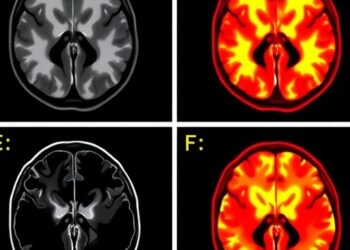

A groundbreaking study published in Molecular Psychiatry on March 5, 2026, has unveiled critical molecular insights into ketamine's rapid antidepressant ...